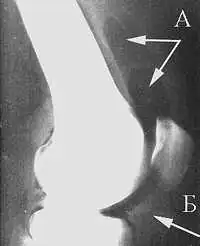

Рентгенологическая семиотика остеоартроза складывается из признаков, отражающих дистрофические изменения в суставных хрящах (сужение суставной щели) и в костной ткани (уплощение и деформация суставных поверхностей, кистовидные образования), нестабильность суставов (подвывихи, искривления оси конечностей), реактивные компенсаторно-приспособительные процессы (краевые костные разрастания, субхондральный остеосклероз).

Ранним рентгенологическим симптомом являются краевые костные разрастания — остеофиты — следствие активной пролиферации периферических отделов суставного хряща. Они проявляются вначале заострением краёв суставных поверхностей, а затем, нарастая, образуют массивные костные шипы и губы. Краевые остеофиты, как правило, раньше обнаруживаются со стороны суставных впадин.

Сужение суставной щели свидетельствует о значительных изменениях суставных хрящей. Суставная щель может стать клиновидной, суживаясь с одной стороны и нередко расширяясь при этом с противоположной, что указывает на недостаточность связочного аппарата и нестабильность сустава.

При остеоартрозе утрачивается амортизационная функция суставных хрящей, предохраняющих костную ткань от механических перегрузок. Как компенсация развивается остеосклероз субхондральной губчатой кости. Особенно он выражен при коксартрозе в крыше вертлужной впадины, распространяясь иногда почти на всё тело подвздошной кости. Однако рано или поздно этот механизм компенсации становится недостаточным. Механические силы, передающиеся непосредственно с одной суставной поверхности на другую, вызывают атрофию от давления их наиболее нагружаемых участков и прежде всего центральных отделов суставных головок. Вследствие этого они уплощаются и одновременно расширяются.

Результатом поражения суставных хрящей являются очаговые дистрофические и некротические процессы в субхондральной губчатой кости, соответствующие локальным пикам механических напряжений. В результате этих процессов формируются кистовидные образования. Последние наиболее характерны для коксартроза, при котором они часто множественны и достигают больших размеров (эрозивный артроз).

- Остеоартроз на I стадии характеризуется главным образом краевыми костными разрастаниями при незначительном сужении суставной щели.

- На II стадии она сужена более отчётливо, возникает субхондральный остеосклероз.

- Резкое сужение суставной щели на III стадии сопровождается уплощением суставных поверхностей и развитием кистовидных образований.

В настоящее время используется рентгенологическая классификация остеоартроза по Kellgren-Lawrence[18][19]:

- I стадия (сомнительный) — сомнительное сужение суставной щели, возможны остеофиты

- II стадия (мягкий) — определённые остеофиты и сомнительное сужение суставной щели

- III стадия (умеренный) — умеренные остеофиты, определённое сужение суставного пространства, возможная деформация костей

- IV стадия (тяжёлый) — большие остеофиты, сужение суставного пространства, тяжёлый остеосклероз, определённая деформация костей